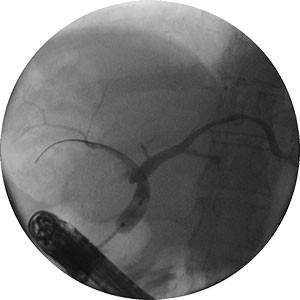

Image of dilation of a stricture with the Hurricane Dilatation Balloon

Dilation of a stricture with the Hurricane Dilatation Balloon